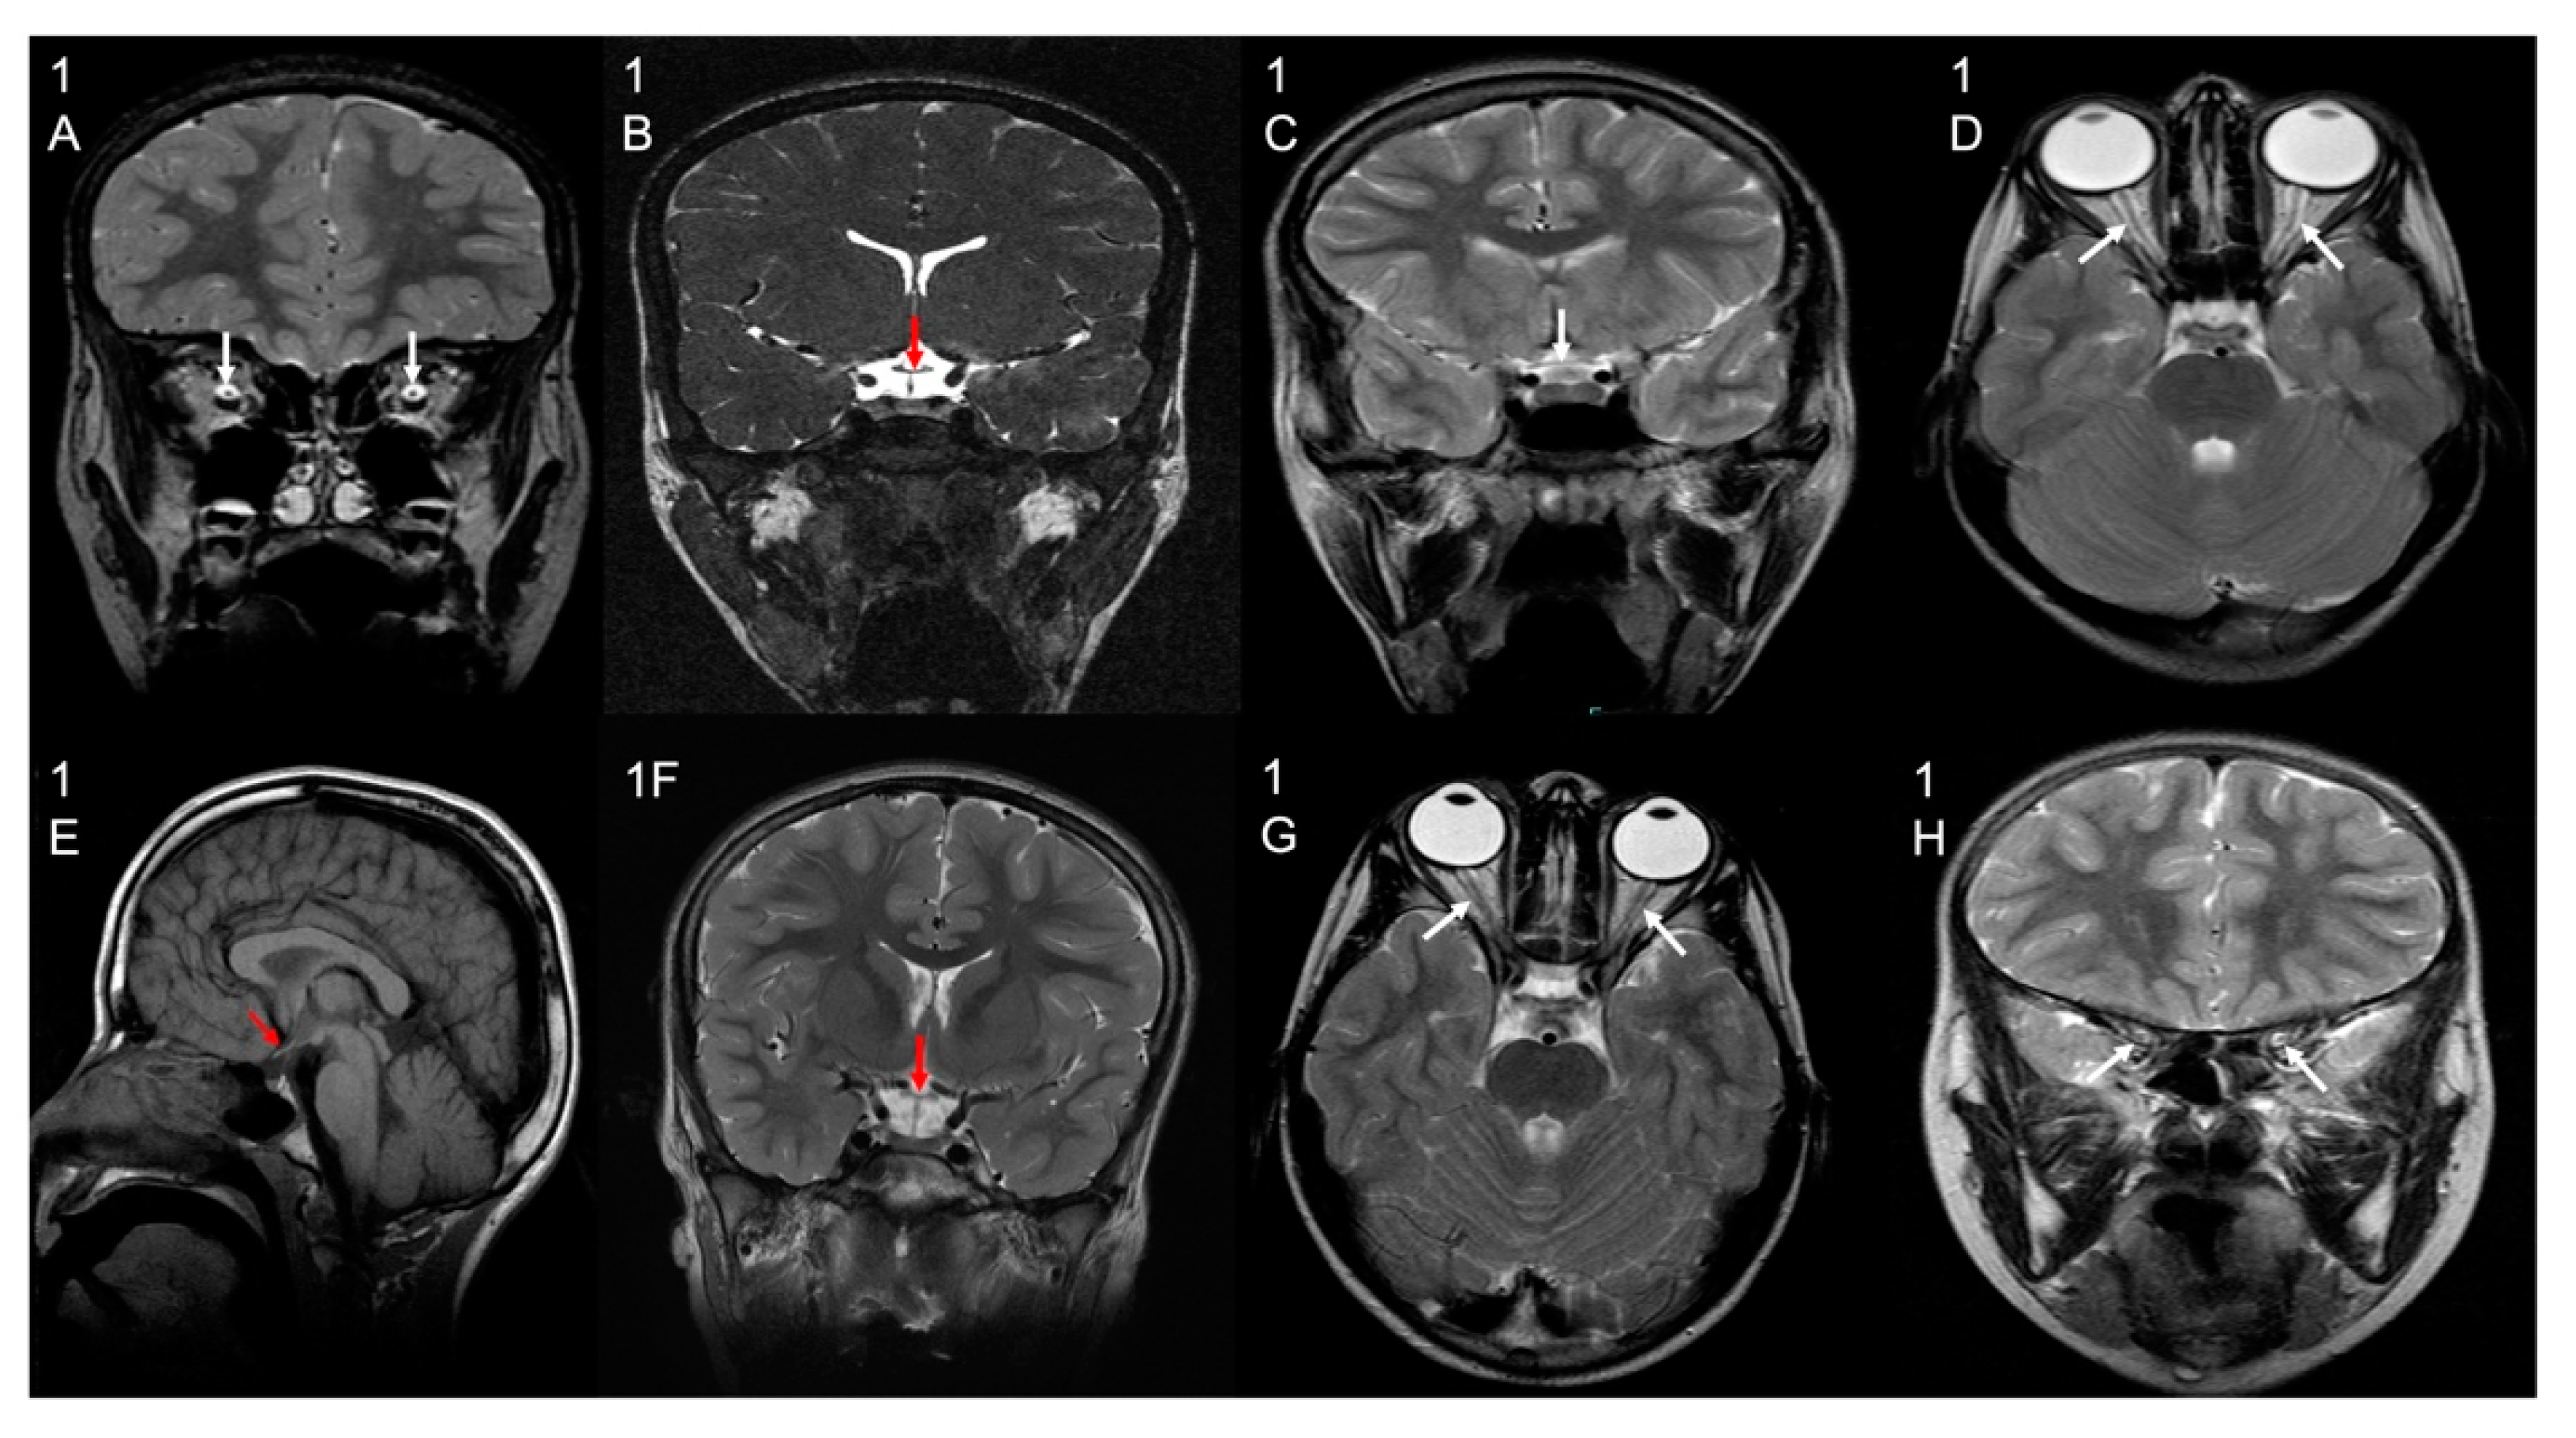

3.2. Brain Imaging Findings